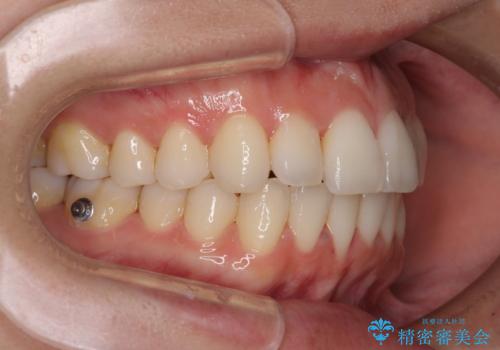

前歯のクロスバイト インビザラインによる矯正治療

- 上下のクロスバイトと前歯のデコボコを気にして来院された患者様です。

インビザラインを用い、IPR(歯と歯の間を削る)と歯列全体を拡大させることで、歯並びを整えていくこととしました。

治療を急いでいらっしゃらなかったため、のんびりと治療を進めていきました。3年以上の期間を要しましたが、きれいな口元に仕上がりました。